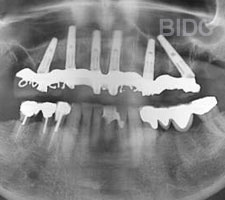

After All-on-4 and All-on-6 cases done at BIDC by implantologists.

2. Installing the implant

If there is existing teeth, teeth are removed. Alevolplasty is commonly done after teeth removal to preserve and shape existing bone. The implant posts is then installed dental implants. The number of implants of 4, 5, 6, or more placed is basded on on bone condition and expected final prothses. If patient requires a temporary dentures during the 3 to 5 days wait time for the fixed hybrid bridge /overdentures, a temporary dentures can be opted prior to start of surgery or your old dentures may be re-lined for wear.

3. Attaching the hybrid bridge

Teeth impression for the hybrid bridge / overdendtdure is taken immediately after teeth implants placement or within the next 2 days. The hybrid bridge / overdenture frame is made in the dental labs. Upon its delivery, the framework is tried on and adjusted before it is securely installed on top of the implants.